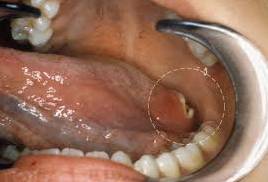

Рак корня языка – фото:

Рак корня языка представляет собой злокачественное новообразование, которое может проявляться различными симптомами. Врачи отмечают, что на ранних стадиях заболевание может быть бессимптомным, что затрудняет его диагностику. По мере прогрессирования опухоли пациенты могут испытывать боль, затруднения при глотании, а также изменения в голосе. Внешний вид опухоли может варьироваться: она может выглядеть как язва, утолщение или даже как белесоватое пятно на поверхности языка. Важно, чтобы пациенты обращались к специалистам при первых признаках дискомфорта, так как ранняя диагностика значительно увеличивает шансы на успешное лечение. Врачи подчеркивают необходимость регулярных осмотров у стоматолога и отоларинголога, особенно для людей с факторами риска.

Рак корня языка — это злокачественное новообразование, которое вызывает множество вопросов и опасений у людей. Многие отмечают, что симптомы могут быть неочевидными на ранних стадиях: это может быть легкий дискомфорт, затрудненное глотание или изменение голоса. Однако, по мере прогрессирования заболевания, пациенты начинают испытывать более выраженные боли и заметные изменения в состоянии языка. Внешний вид рака корня языка может варьироваться: от язвочек и утолщений до красных или белых пятен. Люди часто делятся своими историями о том, как важна ранняя диагностика и регулярные осмотры у врача, так как это может значительно повысить шансы на успешное лечение. Обсуждая эту тему, многие подчеркивают необходимость информирования о симптомах и факторах риска, чтобы повысить осведомленность и помочь другим избежать серьезных последствий.